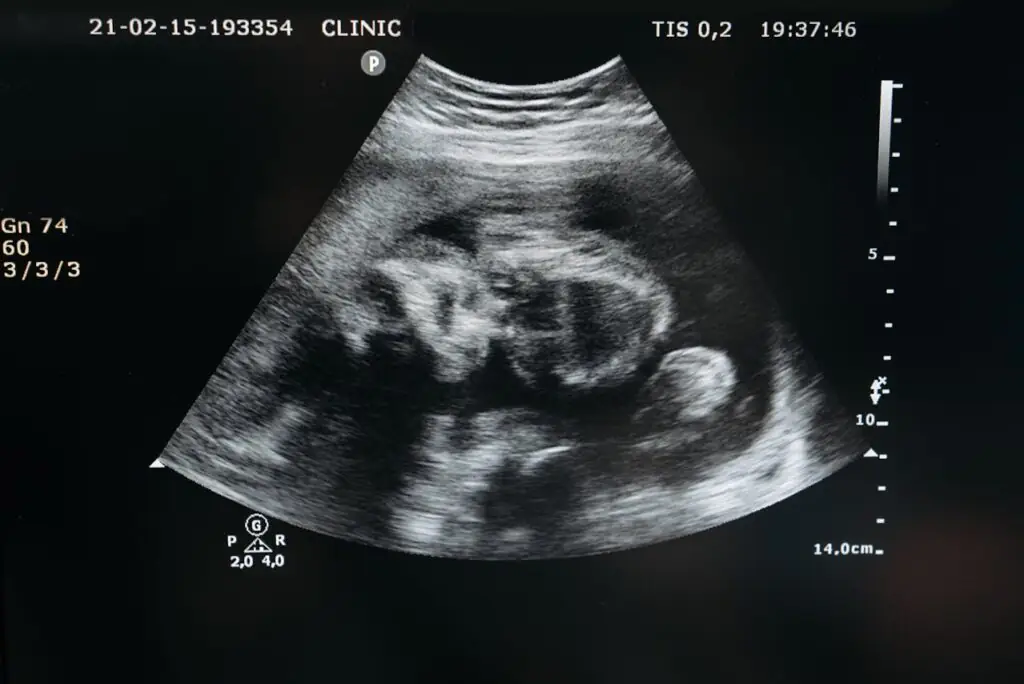

Ultrassonografia

A ultrassonografia transvaginal pode ser útil para detectar cistos relacionados à endometriose (endometriomas), embora não seja capaz de identificar todos os tipos de lesões da endometriose.